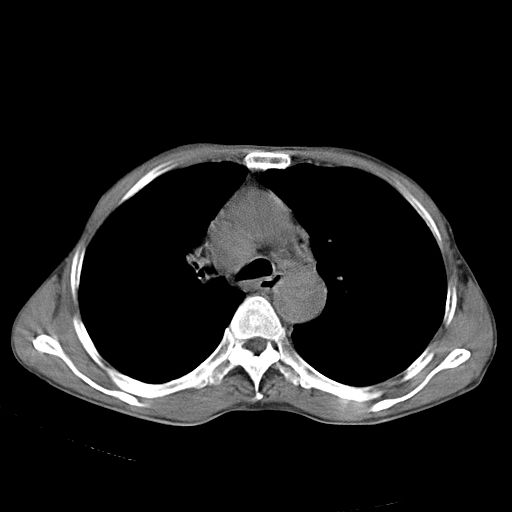

以下是引用苯小孩在2007-5-24 12:47:00的发言:[br]右侧肺门处不均匀密度软组织块影,远端肺组织见斑片模糊影,纵隔内淋巴结明显肿大,边界不清.<纵隔窗第12层面支气管内似见软组织结节>[br]考虑:1、右侧中央性肺癌并阻塞性肺炎并纵隔淋巴结转移可能性大.建议强化或纤支镜进一步检查.[br]2、隆突下淋巴结肿大/食道病变?请做鉴别检查.

以下是引用zhangzhongshou在2007-5-24 12:55:00的发言:[br]1、右肺中叶中心型肺癌并右肺门、隆突下、纵隔淋巴结转移。右肺中叶阻塞性肺炎。

以下是引用jw-830在2007-5-24 15:24:00的发言:[br][br] [br] 考虑右肺中央型肺癌并阻塞性炎症,右肺门及纵隔淋巴结转移。 [br] [br][br]